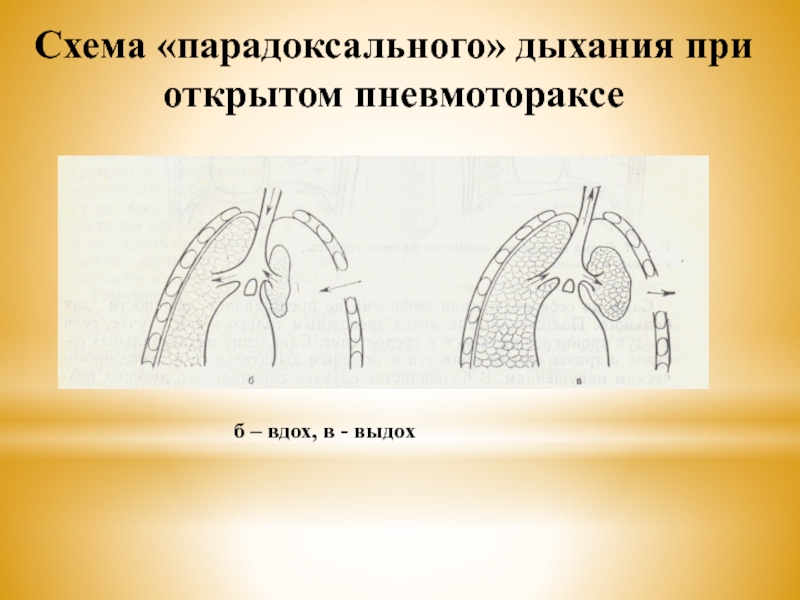

Схемы дыхания: Пневмоторакс на изображениях